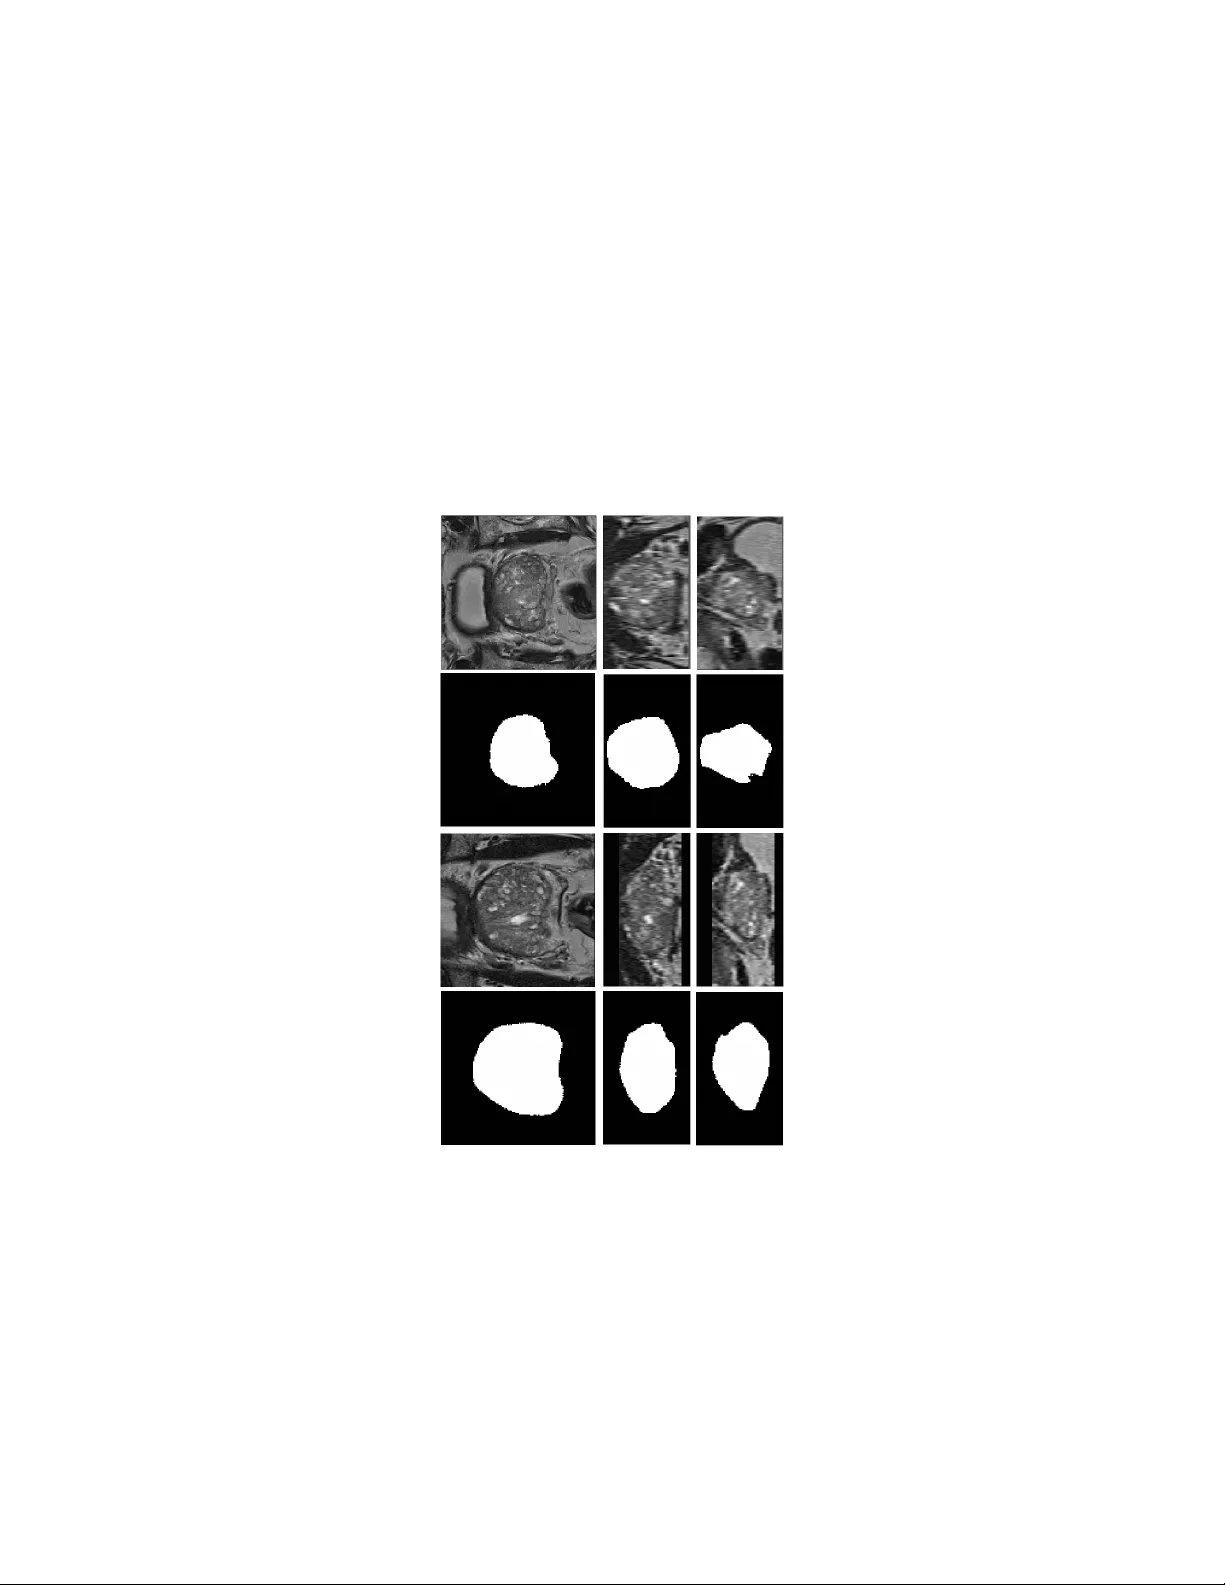

A no v el deep learning-based metho d for prostate seg- men tation in T2-w eigh ted magnetic resonance imaging Da voo d Karimi, Golno osh Samei, Y anan Shao, Septimiu Salcudean Departmen t of Electrical and Computer Engineering, The Universit y of British Colum bia, V ancouver, BC, Canada Abstract W e propose a no vel automatic method for accurate segmen tation of the prostate in T2-w eighted magnetic resonance imaging (MRI). Our metho d is based on conv olutional neural netw orks (CNNs). Because of the large v ariabilit y in the shape, size, and app earance of the prostate and the scarcit y of annotated training data, w e suggest training tw o separate CNNs. A global CNN will determine a prostate b ounding box, whic h is then resampled and sent to a local CNN for accurate delineation of the prostate b oundary . This wa y , the local CNN can effectively learn to seg- men t the fine details that distinguish the prostate from the surrounding tissue using the small amount of av ailable training data. T o fully exploit the training data, we syn thesize additional data by deforming the train- ing images and segmen tations using a learned shape model. W e apply the prop osed method on the PROMISE12 c hallenge dataset and achiev e state of the art results. Our prop osed metho d generates accurate, smooth, and artifact-free segmen tations. On the test images, w e achiev e an av erage Dice score of 90.6 with a small standard deviation of 2.2, which is supe- rior to all previous metho ds. Our t wo-step segmentation approach and data augmentation strategy ma y b e highly effectiv e in segmentation of other organs from small amounts of annotated medical images. 1 In tro duction Segmen tation of the prostate in T2-w eighted magen tic resonance imaging (MRI) is an essential step for many tasks in treatmen t planning and interv ention [22, 53]. Automatic segmentation metho ds are highly desirable b ecause they can increase the sp eed and reproducibility of the segmen tation. In the past decades, man y studies ha ve prop osed (semi-)automatic metho ds for prostate segmen- tation in T2-weigh ted MRI [51, 12, 24]. Ho wev er, fully automatic prostate segmen tation is v ery challenging b ecause of the inter-patien t v ariabilit y in the prostate size, shape, and app earance, v ariations in the scanners and scanning proto cols, and similarit y of the prostate with the surrounding tissue. A large n umber of the metho ds prop osed for prostate segmentation in T2- w eighted MRI use atlases [19, 31]. In these metho ds, a num b er of MR images with known prostate segmen tation are registered to the target image. Mutual information, cross-correlation, image feature correspondence, and the image gra- dien t are among the image similarity metrics used for registration. The deformed prostate segmentation masks of the atlas images are then com bined to infer the 1 segmen tation of the prostate in the target image. Therefore, atlas-based meth- o ds turn the segmen tation problem in to a registration problem. A critical c hoice in these metho ds is how to combine/fuse the registered segmen tation masks. One can rank the segmen tation masks based on some image similarit y metric and choose the most similar segmentation, or use more elaborate metho ds such as ma jorit y voting, simultaneous truth and p erformance level estimation (ST A- PLE), or iterative lab el fusion [6, 19, 21]. In general, atlas-based metho ds are computationally expensive and can pro duce p oor segmen tations, esp ecially if the target image is very differen t from the p opulation of the images in the atlas. T o ac hiev e acceptable results, some atlas-based metho ds rely on additional steps based on statistical shap e mo dels [31, 30, 10]. Moreo ver, most of the atlas-based metho ds follow a global registration strategy , which mak es them unnecessarily sensitiv e to the anatomical features that are far aw ay from the prostate and in- creases the computational time. T o o v ercome these shortcomings, some studies ha ve prop osed tw o-step registration approaches in which a global registration is first p erformed to identify the lo cation of the prostate in the image. In the sec- ond stage, a lo cal registrtation is p erformed by fo cusing on the prostate region [50, 34]. Another class of methods includes those based on deformable models suc h as activ e shap e models and level sets [52, 25, 18, 44, 47]. A great app eal of these metho ds is that they are based on sound theory from physical sciences and mathematics. How ever, these metho ds can b e very sensitive to initialization [45] and a go od initialization may b e hard to obtain. Moreov er, the quality of segmen tation can b e p oor, esp ecially where the edge information is not strong. Therefore, some of these metho ds dep end on man ual initialization or rely on other prioir information in the form of shap e models to regularize or refine the generated segmen tation [48, 5]. Some studies ha ve prop osed methods based on graph cuts [8, 27]. Although these metho ds are versatile, they hav e their own limitations. F or example, they pro duce p oor results at the lo cations of weak edges and typically need p ost-processing steps in order to obtain satisfactory results. Recen tly , some studies hav e shown that the p erformance of graph cut-based metho ds can b e substan tially improv ed by using activ e contours and b y form ulating the graph cut metho d in terms of super-vo xels instead of raw vo xel intensities [41, 42]. Because of the difficulties faced b y the methods mentioned ab o v e, a large n umber of studies hav e tried to combine the adv antages of tw o or more of these framew orks. Many of these metho ds also use some t yp e of mac hine learning to ac hieve impro v ed results. F or example, several studies ha ve com bined proba- bilistic learning of the distribution of prostate texture or vo xel intensities with shap e mo dels [43, 29, 1]. Sup ervised and un-sup ervised machine learning meth- o ds such as random forests and clustering metho ds hav e also been com bined with deformable mo dels and atlas-based methods for prostate semen tation in T2-w eighted MRI [28, 11, 9]. One study has suggested using shape models in the framew ork of marginal space learning for prostate segmentation in T2-weigh ted MRI [2] Despite the great efforts and n umerous metho ds that hav e b een prop osed in 2 recen t years, automatic segmentation of the prostate in T2-weigh ted MRI still remains a challenge. Most of the proposed metho ds achiev e muc h low er per- formance than manual segmentation. If the test images are v ery different from the images used for model developmen t, e.g., due to in ter-patient v ariabilit y or differen t scanning proto cols, the p erformance of these metho ds can deteriorate substan tially . In recent years, deep conv olutional neural net w orks (CNNs) hav e achiev ed unpreceden ted results in segmentation of natural images [26, 3, 33]. Compared to the more traditional segmentation metho ds, the new CNN architectures that ha ve been proposed for dense segmen tation p ossess a n umber of highly desirable c haracteristics: 1) they hav e a very high capacit y that enables them to effectively describ e the large v ariations that exist in the training data, 2) they are able to explain lo cal and global information at differen t resolutions simultaneously , 3) in many applications they can ac hieve quite satisfactory results without the need to additional post-pro cessing steps to refine their segmen tation, which also implies that they can b e trained end-to-end as a single mo dule, and 4) ev en though they ha v e long training times, their inference time is very fast. Consequen tly , many studies hav e recen tly emplo yed CNNs for segmentation of medical images [23] and, in general, they hav e rep orted v ery promising results. F or segmentation of the prostate in T2-w eighted MRI, in particular, deep CNNs with volumetric conv olutional filters hav e b een shown to ac hieve v ery go o d results [32]. One study resampled the ground-truth segmen tation to generate prostate masks with differen t resolutions for more effectiv e training of a deep CNN [49]. The trained CNN w as applied on sub-volumes of the input image and a veraging of the probability maps estimated for all sub-v olumes w as used to obtain the final prostate segmentation. The proposed metho d achiev ed state of the art results, which w as also attributed to the use of short and long residual connections in the netw ork. Another study prop osed a deep CNN with 2D and 3D residual connections and achiev ed state of the art results [37]. Karimi et al. prop osed to segmen t the prostate in MR images using a no vel netw ork arc hitecture that predicted the lo cation, orien tation, and the coefficients of a statistical shap e model [16]. In this pap er, we propose a new CNN-based metho d for segmentation of the prostate in T2-weigh ted MR images. W e argue that the difficulty in achiev- ing h uman-level p erformance in this task is due to the large v ariabilit y in the shap e, size, and app earance of the prostate in these images. Based on the results achiev ed by CNNs in segmentation of natural images, w e think that the- oretically they should be able to ac hieve human-lev el p erformance in prostate segmen tation in T2-weigh ted MRI. How ever, this is not e asy to achiev e in prac- tice b ecause it is hard to effectiv ely train large CNNs with small amounts of annotated data. T o reduce this gap and effectively utilize the capacit y of deep CNNs with limited training data, w e suggest tw o strategies: 1. W e suggest training tw o CNNs. The first, glob al , CNN will accept the en tire image as its input and generate a soft prostate segmentation mask. This initial segmentation is then used to determine the lo cation and the 3 exten t of the prostate in the image. A second, lo c al , CNN will then work on a sub-volume of the image that is resampled from the input image in suc h a w a y that the prostate is approximately at the cen ter of the v olume and has an appro ximately fixed size. This will allo w the lo cal CNN to fo cus on learning features that are most relev an t for accurate delineation of the prostate boundary , whic h is a ma jor c hallenge due to similarity with the surrounding tissue, large v ariability , and scarcit y of training data. 2. W e use massive data augmen tation for training of the tw o CNNs. Here, our argumen t is that even 50 training images are not sufficient to train large CNNs. Therefore, we syn thesize additional realistic data by deforming the training images and their segmen tation masks using displacement fields that are computed based on a prostate shap e mo del. T o further improv e the training and av oid lo cal minima, random displacements and noise are in troduced during training. Moreo ver, using cross-v alidation we will iden tify the images that are most difficult to segmen t and will use this information in training our final mo del. 2 Materials and metho ds A schematic represen tation of the steps inv olved in our fully-automatic segmen- tation metho d is sho wn in Figure 1. Considering the great v ariabilit y in the shap e, size, texture, and appearance of the prostate and its surrounding organs and the limited av ailabilit y of training data, we suggest learning tw o separate CNNs. After some pre-pro cessing steps, the input image is passed to a global CNN, whic h generates an initial soft segmen tation of the prostate. W e will use this initial segmen tation, along with a prostate shap e mo del, to identify the lo cation and the extent of the prostate in the image. Using this information, we extract a v olume of interest that contains the prostate and send it to a second, lo cal, CNN that accurately delineates the prostate b oundary . Basic thresholding and post-pro cessing steps on the output probabilit y map of the lo cal CNN will generate the final prostate segmen tation mask. In the follo wing sub-sections, w e first pro vide a description of the steps in volv ed in our proposed segmentation metho d. W e will then pro vide more detailed information on v arious steps. 2.1 Steps of the prop osed segmentation metho d As shown in Figure 1, giv en a test image the follo wing steps are p erformed to generate the prostate segmen tation mask. Pre-pro cessing First, a bias correction is applied to the image using the N4ITK algorithm [39, 46]. The image is resampled to an isotropic v o xel size of 1 mm 3 . A volume of size 128 × 128 × 72 vo xels is then created, us- ing either centered-cropping or zero-padding if the image is, resp ectiv ely , larger or smaller than this desired size in each dimension. Finally , the im- 4 age is normalized such that the vo xels hav e a mean of zero and a standard deviation of one. Determining the prostate location and extent The pre-pro cessed 128 × 128 × 72-vo xel image is sent to the global CNN. The output of this net work is a probabilit y map where the v alue of each vo xel sho ws the probability of that v o xel b elonging to the prostate. As we will show in the Results section, this probabilit y map itself pro vides a goo d segmentation of the prostate. Ho wev er, in our metho d we will treat it as an initial segmenta- tion that is used only to identify the location and the extent of the prostate in the image. The center of mass of this segmentation can give us an ac- curate estimation of the location of the cen ter of the prostate. How ever, in order to obtain an accurate estimation of the extent of the prostate, w e need to remo ve the possible outlier v o xels. F or this purpose, we fit a prostate shape model to the learned probability map using a particle sw arm optimization algorithm. Fine segmentation of the prostate Given the information on the lo cation and the exten t of the prostate from the ab ov e step, the pre-pro cessed MR image is resampled again to generate an input for the lo cal CNN. Similar to the global CNN, the local CNN has an input size of 128 × 128 × 72 vo xels. Ho wev er, whereas the input to the global CNN has an isotropic vo xel size of 1 mm 3 , the input to the local CNN is generated suc h that the prostate is at the cen ter and has a pre-determined size. Specifically , in this stage w e resample the image such that the prostate has a size of approximately 80 × 80 × 48 v oxels. F or example, if the prostate size estimated using the global CNN is 40 × 32 × 36 mm, the MR image is resampled to hav e a v oxel size of 0 . 50 × 0 . 40 × 0 . 75 mm such that the prostate in the resampled image has, appro ximately , the desired size of 80 × 80 × 48 v oxels. This resampled volume of interest is passed to the lo cal CNN, which estimates Figure 1: A schematic represen tation of the steps inv olved in the prop osed segmen tation metho d. 5 a more accurate segmen tation of the prostate. P ost-pro cessing The probability map pro duced b y the lo cal CNN, thresh- olded at 0.50, constitutes our p enultimate prostate segmen tation. Our p ost-processing consists only of applying an opening op eration (erosion follo wed by dilation) [38] using a spherical structuring elemen t with a radius of 2 mm. This op eration will remo ve the o ccasional non-smo oth artifacts on the surface of the prostate mask obtained by thresholding the probabilit y map. 2.2 CNN arc hitecture The CNN arc hitecture used in this study tak es adv an tage of man y of the ef- fectiv e CNN design practices. A sc hematic represen tation of this arc hitecture is sho wn in Figure 2. The netw ork has a contracting and an expanding path that enable it to learn features at fine and coarse resolutions [35, 4]. In the con tracting path, the netw ork computes conv olutional feature maps with k er- nels of increasing size k ∈ { 3 , 5 , ..., 2 d + 1 } and stride s ∈ { 1 , 2 , ..., d } . The net work sho wn in Figure 2 is for d = 4. These conv olutional feature maps will capture different levels of detail directly in the source image. In each resolution lev el, a residual mo dule with short and long skip connections is used to increase the expressiveness of these features and netw ork’s capacit y and also make the training faster [14, 7]. Each of the computed feature maps is passed forw ard to all low er lev els b y applying conv olutional filters with the prop er stride. This will promote feature reuse and make the training easier by reducing the num b er of parameters and improving the gradient flow [15]. Therefore, in the con- tracting path the num b er of feature maps geometrically increases while their size becomes smaller. The computed features then go through a series of up- con volutions in order to build up the prostate segmentation mask. Thsi pro cess will start from the low-resolution feature maps of the con tracting path, which moslt y con tain coarse information. In order to aid reco v ery of the fine detail, the m ulti-resolution information a v ailable in the feature maps of the con tracting path is re-in tro duced into the expanding path via concate nating those feature maps to the feature maps of the expanding path. Residual mo dules, similar to those in the con tracting path, are also applied here in the expanding path. All con volutional and up-con volutional lay ers, except for those applied directly on the input MR image, use k ernels of size 3. F urthermore, all these lay ers, except for the last are follow ed b y rectified linear units [20]. The final feature map, which has the same dimensions as the source image is passed to a final con volutional la yer follo wed by a soft-max op eration to produce a pixel-wise probabilit y map of the prostate. Both CNNs follow the same architecture as shown in Figure 2, except that they hav e different depths. W e found that for the global CNN the results were impro ved as w e increased the net w ork depth to d = 5. W e think this is b ecause the low-resolution feature maps hav e a larger field of view that enables them to learn features that b etter represent the lo cation and extent of the prostate in 6 Figure 2: A sc hematic represen tation of the CNN arc hitecture used in this study . The netw ork s ho wn in this figure has a depth of 4. The global and lo cal net works used in this study had depths of 5 and 3, resp ectiv ely . the image. F or the lo cal CNN, how ever, a shallow er netw ork with a depth d = 3 led to b etter results. This is b ecause the input to this netw ork is a resampled v olume of interest in whic h the prostate is approximately at the center and has appro ximately a fixed pre-determined size. Therefore, the lo cal CNN do es not ha ve to learn to estimate the lo cation or the extent of the prostate but only to delineate the prostate boundary . Therefore, for the lo cal CNN increasing the depth unnecessarily increases the n umber of netw ork parameters and in tro duces coarse features that do not contribute substan tially to the delineation of the prostate b oundary . 2.3 T raining and ev aluation W e used the data from the PROMISE12 c hallenge [24]. This dataset consists of 50 training and 30 test images, whic h ha ve b een acquired at different centers and using different scanners and scanning proto cols. The dataset is very c hallenging b ecause of the large v ariation in the vo xel size, field of view, and dynamic range of the images as well as in the app earance of the prostate. Approximately half of the images include an endorectal coil. W e used a five-fold cross v alidation approach to determine the netw ork size, n umber of features and other imp ortan t training parameters such as the learning rate sc heduling and the dropout rate. Each time, the t wo CNNs w ere trained on 40 of the images and ev aluated on the remaining 10 images. Ha ving found the optimal net w ork size and learning parameters using cross-v alidation, the final global and local CNNs were trained on all 50 training images and applied on the 30 test images. The final global and local CNNs w ere both initialized at random using He’s method [13] and trained using Adam’s metho d [17] with a batch size 7 of one to maximize the Dice score b etw een the output probabilit y m ap of the net work and the ground-truth segmentation mask. T raining was p erformed for 1000 ep ochs. The starting learning rate was 10 − 5 , which was m ultiplied by 0.5 when the training cost function plateaued. In order to cop e with the limited training data, w e use a data augmentation sc heme based on a learned shape mo del. In this strategy , the training images and its labels are deformed using displacemen ts suggested b y a learned shape model. Moreo ver, we add white Gaussian noise with a standard deviation of 0.03 to each image at each training step. T o further reduce the risk of o verfitting, we use drop out [40] with a rate of 0.15 on all con volutional la yers in the net work. This drop out rate significantly reduced the o v erfitting suc h that the segmentation p erformance on the training and v alidation images w as almost equal. 3 Results and discussion T able 1 sho ws the a verage and standard deviation of the Dice score on the training, v alidation, and test images. In order to show the effect of the different steps in our segmentation pipeline, w e hav e shown the resulting Dice score after eac h step. Our prop osed metho d achiev es a high final Dice score of 90 . 6 with a lo w standard deviation of 2 . 2. Global CNN Local CNN Post-processing T raining 85 . 0 ± 3 . 9 91 . 0 ± 2 . 3 91 . 2 ± 2 . 2 V alidation 84 . 9 ± 4 . 1 90 . 4 ± 2 . 3 91 . 2 ± 2 . 0 T est 85 . 4 ± 3 . 6 90 . 2 ± 2 . 4 90 . 6 ± 2 . 2 T able 1: Mean ± standard deviation of the Dice score for training, v alidation, and test images after eac h step in the segmentation pip eline. A test image and its prostate segmen tation masks produced by the global and local CNNs in axial, sagittal, and coronal directions are sho wn in Figure 3. The accuracy of segmen tation of the global CNN is not very high. The Dice score achiev ed by the global CNN is 85 . 4 ± 3 . 6, which is substan tially lo wer than that ac hieved b y the lo cal CNN (90 . 2 ± 2 . 4). Nonetheless, as w e mentioned ab o v e, our metho d uses the segmentation provided by the global CNN only to estimate the lo cation and exten t of the prostate in the image. Our results show that it is possible to accurately extract this information from the probability map produced by the global CNN. The error in the estimation of the start and end of the prostate in axial, sagittal, and coronal directions were, resp ectiv ely , 0 . 8 ± 0 . 9, 1 . 4 ± 1 . 5, and 1 . 2 ± 1 . 0 millimeters, and the error in estimating the size of the prostate in these three directions were, 1 . 6 ± 1 . 4, 2 . 2 ± 2 . 0, and 2 . 1 ± 1 . 7 millimeters, resp ectiv ely . These errors are quite within the range of acceptable error range for our intended goal. Using the information on the size and location of the prostate in the image, a 128 × 128 × 72-vo xel v olume is resampled such that the prostate is approximately at the center and has a size of 80 × 80 × 48 v oxels. As can b e seen in the example image shown in Figure 3, dep ending on 8 the size of the MR image and the size and lo cation of the prostate, this ma y lead to stretching or shrinking of the image in different directions and may need cropping or zero padding. Ho wev er, it will ensure that the prostate is at the cen ter of the volume and has a pre-determined size, allowing the local CNN to ac hieve sup erior segmen tation accuracy . As can b e seen in Figure 3, the lo cal CNN generates an accurate segmen tation mask that usually does not need any p ost-processing. Ho w ever, in our metho d w e alwa ys p erform a morphological op ening op eration that remov es any small non-smo oth features caused by hard- thresholding the output probability map of the lo cal CNN. As shown in T able 1, this operation has a noticeable p ositive effect on the a verage Dice coefficient. Figure 3: The prostate segmentation masks pro duced b y the global and lo cal CNNs. The first row sho ws the 128 × 128 × 72-v oxel image sen t to the global CNN. The second row shows the segmen tation mask produced b y the global CNN. The third ro w sho ws the volume resampled from the input image to b e used b y the lo cal CNN. The last ro w sho ws the prostate segmentation mask pro duced b y the lo cal CNN. 9 More examples of the p erformance of the prop osed segmen tation algorithm on test images are shown in Figure 4. They further demonstrate that the pro- p osed method is able to accurately segment the prostate. As the n umbers in T able 1 suggest, one of the reasons for the success of the proposed metho d is the t wo-step segmentation metho d that enables the lo cal CNN to achiev e sup erior results. As w e argued ab ov e, the v ariability in the shap e, size, and app earance of the prostate and it surrounding anatomy is very high. Although large CNNs ha ve the capacit y to capture such complexit y , the amount of training data is not large enough to realize their full p otential. Therefore, in the absence of v ery large datasets as those av ailable for natural images [36], it will be very difficult to achiev e segmentation accuracies close to human experts. Our strat- egy of training t w o separate CNNs eases the situation b y introducing a division of lab or in whic h the global CNN is only exp ected to produce a s egmen tation that is accurate enough to estimate the lo cation and size of the prostate while the lo cal CNN is giv en a well-formatted input that makes it easy to accurately segmen t the prostate b oundary . Figure 4: The prostate segmentation masks pro duced b y the global and lo cal CNNs. The first row sho ws the 128 × 128 × 72-v oxel image sen t to the global CNN. The second row shows the segmen tation mask produced b y the global CNN. The third ro w sho ws the volume resampled from the input image to b e used b y the lo cal CNN. The last ro w sho ws the prostate segmentation mask pro duced b y the lo cal CNN. Another imp ortan t factor that contributes to the p erformance of our pro- p osed method is data augmentation. In order to examine the impact of data aug- men tation, we trained the CNNs without any data augmen tation and ac hieved a final Dice s core of 86 . 1 ± 6 . 6. Another widely used data augmen tation strategy is to deform the image and its segmentation mask using a random deforma- 10 tion field. W e found that this strategy was also very useful in pushing the p erformance of our prop osed method, but achiev ed a sligh tly low er Dice score 0 . 893 ± 0 . 040 that our augmen tation approach based on shap e mo dels. Another imp ortan t factor in our optimization is the careful c hoice of the drop out rate. Dropout is kno wn to be essen tial in net works with large fully- connected lay ers. How ever, its imp ortance is usually assumed to b e less signif- ican t in the conv olutional lay ers [40]. How ever, our exp erimen ts sho w ed that, esp ecially for ac hieving sup erior p erformance in the local CNN, it was necessary to choose a drop out rate of 10 − 20%. This ensured that training and v alidation p erformance w ere very close and the netw ork conv erged nicely , whereas without drop out our method achiev ed a go od p erformance on the training set but 4 Conclusion Deep learning mo dels ha ve b een v ery successful for medical image segmentation. Giv en the small size of t ypical datasets, training of these mo dels is c hallenging. In this work, we show ed that for prostate segmen tation in MRI, an effective approac h is to p erform the segmen tation in tw o stages: in Stage One the prostate is lo cated and roughly segmented; in Stage Tw o, the prostate is accurately delineated using the b ounding box obtained from Stage One. A similar proce dure as that prop osed in this pap er for prostate segmentation in MRI ma y b e useful for other medical image segmentation applications. References [1] Philip D Allen, James Graham, David C Williamson, and Charles E Hutc hinson. Differen tial segmentation of the prostate in mr images us- ing com bined 3d shap e mo delling and vo xel classification. In Biome dic al Imaging: Nano to Macr o, 2006. 3r d IEEE International Symp osium on , pages 410–413. IEEE, 2006. [2] Neil Birkb ec k, Jingdan Zhang, Martin Requardt, Berthold Kiefer, and Pe- ter Gall. Region-specific hierarchical segmen tation of mr prostate using discriminativ e learning. [3] Liang-Chieh Chen, George P apandreou, Iasonas Kokkinos, Kevin Murphy , and Alan L. Y uille. Deeplab: Semantic image segmentation with deep con volutional nets, atrous con volution, and fully connected crfs. CoRR , abs/1606.00915, 2016. [4] ¨ Ozg ¨ un C ¸ i¸ cek, Ahmed Ab dulk adir, So eren S Lienk amp, Thomas Brox, and Olaf Ronneberger. 3d u-net: learning dense v olumetric segmen tation from sparse annotation. In International Confer enc e on Me dic al Image Comput- ing and Computer-Assiste d Intervention , pages 424–432. Springer, 2016. 11 [5] Timothy F Co otes, Andrew Hill, Christopher J T aylor, and Jane Haslam. The use of active shap e mo dels for locating structures in medical images. In Biennial International Confer enc e on Information Pr o c essing in Me dic al Imaging , pages 33–47. Springer, 1993. [6] Jason A Dowling, Jurgen F ripp, Shekhar Chandra, Josien P W Pluim, Jonathan Lambert, Joel P arker, James Denham, P eter B Greer, and Olivier Salv ado. F ast automatic m ulti-atlas segmen tation of the prostate from 3d mr images. In International Workshop on Pr ostate Canc er Imaging , pages 10–21. Springer, 2011. [7] Michal Drozdzal, Eugene V oron tsov, Gabriel Chartrand, Samuel Kadoury , and Chris P al. The importance of skip connections in biomedical image segmen tation. In International Workshop on L ar ge-Sc ale Annotation of Biome dic al Data and Exp ert L ab el Synthesis , pages 179–187. Springer, 2016. [8] Jan Egger. Pcg-cut: graph driv en segmen tation of the prostate central gland. PloS one , 8(10):e76645, 2013. [9] Qinquan Gao, Aksha y Asthana, T ong T ong, Yip eng Hu, Daniel Ruec kert, and Philip Edwards. Hybrid decision forests for prostate segmen tation in m ulti-channel mr images. In Pattern R e c o gnition (ICPR), 2014 22nd International Confer enc e on , pages 3298–3303. IEEE, 2014. [10] Y. Gao, R. Sandhu, G. Fich tinger, and A. R. T annenbaum. A coupled global registration and segmentation framework with application to mag- netic resonance prostate imagery . IEEE T r ansactions on Me dic al Imaging , 29(10):1781–1794, Oct 2010. [11] Soumy a Ghose, Jhimli Mitra, Arnau Oliver, R Mart ´ ı, Xavier Llad´ o, Jordi F reixenet, Joan C Vilanov a, D´ esir ´ e Sidib ´ e, and F abrice Meriaudeau. A random forest based classification approac h to prostate se gmen tation in mri. MICCAI Gr and Chal lenge: Pr ostate MR Image Se gmentation , 2012, 2012. [12] Soumy a Ghose, Arnau Oliv er, Robert Mart ´ ı, Xavier Llad´ o, Joan C Vi- lano v a, Jordi F reixenet, Jhimli Mitra, D ´ esir´ e Sidib´ e, and F abrice Meri- audeau. A survey of prostate segmen tation methodologies in ultrasound, magnetic resonance and computed tomography images. Computer metho ds and pr o gr ams in biome dicine , 108(1):262–287, 2012. [13] Kaiming He, Xiangyu Zhang, Shaoqing Ren, and Jian Sun. Delving deep in to rectifiers: Surpassing h uman-level p erformance on imagenet classifica- tion. In IEEE International Confer enc e on Computer Vision (ICCV) 2015 , 2015. [14] Kaiming He, Xiangyu Zhang, Shao qing Ren, and Jian Sun. Deep residual learning for image recognition. In Computer Vision and Pattern R e c o gni- tion (CVPR), 2016 IEEE Confer enc e on , 2016. 12 [15] Gao Huang, Zhuang Liu, Kilian Q W einberger, and Laurens v an der Maaten. Densely connected conv olutional net works. arXiv pr eprint arXiv:1608.06993 , 2016. [16] Dav o od Karimi, Golno osh Samei, Claudia Kesch, Guy Nir, and Septi- miu E Salcudean. Prostate segmentation in mri using a conv olutional neu- ral netw ork architecture and training strategy based on statistical shape mo dels. International journal of c omputer assiste d r adiolo gy and sur gery , 13(8):1211–1219, 2018. [17] Diederik P . Kingma and Jimm y Ba. Adam: A metho d for sto chastic opti- mization. In Pr o c e e dings of the 3r d International Confer enc e on L e arning R epr esentations (ICLR) , 2014. [18] Matthias Kirschner, Florian Jung, and Stefan W esarg. Automatic prostate segmen tation in mr images with a probabilistic active shape mo del. MIC- CAI Gr and Chal lenge: Pr ostate MR Image Se gmentation , 2012, 2012. [19] Stefan Klein, Uulk e A. v an der Heide, Irene M. Lips, Marco v an V ulp en, Marius Staring, and Josien P . W. Pluim. Automatic segmentation of the prostate in 3d mr images by atlas matc hing using lo calized mutual infor- mation. Me dic al Physics , 35(4):1407–1417, 2008. [20] Alex Krizhevsky , Ily a Sutskev er, and Geoffrey E Hin ton. Imagenet clas- sification with deep conv olutional neural netw orks. In A dvanc es in neur al information pr o c essing systems , pages 1097–1105, 2012. [21] Thomas Robin Langerak, Uulk e A v an der Heide, Alexis NTJ Kotte, Max A Viergev er, Marco V an V ulp en, and Josien PW Pluim. Label fusion in atlas-based segmentation using a selective and iterativ e metho d for perfor- mance level estimation (simple). IEEE tr ansactions on me dic al imaging , 29(12):2000–2008, 2010. [22] Scott Leslie, Alvin Goh, Pierre-Marie Lew ando wski, Eric Yi-Hsiu Huang, Andre Luis de Castro Abreu, Andre K Berger, Hamed Ahmadi, Isuru Ja- y aratna, Sunao Sho ji, Inderbir S Gill, et al. 2050 contemporary image- guided targeted prostate biopsy b etter c haracterizes cancer volume, glea- son grade and its 3d location compared to systematic biopsy . The Journal of Ur olo gy , 187(4):e827, 2012. [23] Geert Litjens, Thijs Kooi, Babak Eh teshami Bejnordi, Arnaud Arindra Adiy oso Setio, F rancesco Ciompi, Mohsen Ghafo orian, Jero en A.W.M. v an der Laak, Bram v an Ginnek en, and Clara I. Snc hez. A surv ey on deep learning in medical image analysis. Me dic al Image Analysis , 42(Supplemen t C):60 – 88, 2017. [24] Geert Litjens, Rob ert T oth, W endy v an de V en, Caroline Ho eks, Sjo erd Kerkstra, Bram v an Ginnek en, Graham Vincent, Gw enael Guillard, Neil 13 Birb ec k, Jindang Zhang, et al. Ev aluation of prostate segmen tation algo- rithms for mri: the promise12 c hallenge. Me dic al image analysis , 18(2):359– 373, 2014. [25] Xin Liu, DL Langer, MA Haider, TH V an der Kw ast, AJ Ev ans, MN W er- nic k, and IS Y etik. Unsup ervised segmen tation of the prostate using mr images based on level set with a shap e prior. In Engine ering in Me dicine and Biolo gy So ciety, 2009. EMBC 2009. A nnual International Confer enc e of the IEEE , pages 3613–3616. IEEE, 2009. [26] Jonathan Long, Ev an Shelhamer, and T revor Darrell. F ully conv olutional net works for semantic segmen tation. In Pr o c e e dings of the IEEE Confer enc e on Computer Vision and Pattern R e c o gn ition , pages 3431–3440, 2015. [27] D. Mahapatra and J. M. Buhmann. Prostate mri segmentation us- ing learned seman tic knowledge and graph cuts. IEEE T r ansactions on Biome dic al Engine ering , 61(3):756–764, March 2014. [28] Nasr Makni, Nacim Betrouni, and Olivier Colot. Introducing spatial neigh- b ourhoo d in eviden tial c-means for segmen tation of m ulti-source images: Application to prostate m ulti-parametric mri. Information F usion , 19(Sup- plemen t C):61 – 72, 2014. Special Issue on Information F usion in Medical Image Computing and Systems. [29] Nasr Makni, P . Puech, R. Lopes, A. S. Dew alle, O. Colot, and N. Be- trouni. Com bining a deformable mo del and a probabilistic framework for an automatic 3d segmen tation of prostate on mri. International Journal of Computer Assiste d R adiolo gy and Sur gery , 4(2):181, Dec 2008. [30] S´ ebastien Martin, Vincen t Daanen, and Jo celyne T ro ccaz. A tlas-based prostate segmentation using an hybrid registration. International Journal of Computer Assiste d R adiolo gy and Sur gery , 3(6):485–492, 2008. [31] Sbastien Martin, Jo celyne T ro ccaz, and Vincent Daanen. Automated seg- men tation of the prostate in 3d mr images using a probabilistic atlas and a spatially constrained deformable mo del. Me dic al Physics , 37(4):1579–1590, 2010. [32] F austo Milletari, Nassir Na v ab, and Seyed-Ahmad Ahmadi. V-net: F ully con volutional neural netw orks for v olumetric medical image segmen tation. In 3D Vision (3DV), 2016 F ourth International Confer enc e on , pages 565– 571. IEEE, 2016. [33] Hyeon woo Noh, Seungho on Hong, and Boh yung Han. Learning decon- v olution netw ork for seman tic segmentation. In The IEEE International Confer enc e on Computer Vision (ICCV) , December 2015. [34] Y angming Ou, Jimit Doshi, Guray Erus, and Christos Dav atzikos. Multi- atlas segmentation of the prostate: A zooming process with robust regis- tration and atlas selection. MICCAI Gr and Chal lenge: Pr ostate MR Image Se gmentation , 2012, 2012. 14 [35] Olaf Ronneb erger, Philipp Fisc her, and Thomas Brox. U-net: Conv olu- tional netw orks for biomedical image segmentation. In International Con- fer enc e on Me dic al Image Computing and Computer-Assiste d Intervention , pages 234–241. Springer In ternational Publishing, 2015. [36] Olga Russak ovsky , Jia Deng, Hao Su, Jonathan Krause, Sanjeev Satheesh, Sean Ma, Zhiheng Huang, Andrej Karpathy , Adity a Khosla, Michael Bern- stein, et al. Imagenet large scale visual recognition challenge. International Journal of Computer Vision , 115(3):211–252, 2015. [37] Bruno Sciolla, Matthieu Martin, and Philipp e Delac hartre. Multi-pass 3d con volutional neural netw ork segmentation of prostate mri images. 2017. [38] Jean Serra. Introduction to mathematical morphology . Computer vision, gr aphics, and image pr o c essing , 35(3):283–305, 1986. [39] John G Sled, Alex P Zijden b os, and Alan C Ev ans. A nonparametric metho d for automatic correction of intensit y non uniformity in mri data. IEEE tr ansactions on me dic al imaging , 17(1):87–97, 1998. [40] Nitish Sriv astav a, Geoffrey E Hinton, Alex Krizhevsky , Ilya Sutskev er, and Ruslan Salakhutdino v. Drop out: a simple wa y to preven t neural netw orks from ov erfitting. Journal of machine le arning r ese ar ch , 15(1):1929–1958, 2014. [41] Zhiqiang Tian, Lizhi Liu, Zhenfeng Zhang, and Bao wei F ei. Superpixel- based segmentation for 3d prostate mr images. IEEE tr ansactions on me d- ic al imaging , 35(3):791–801, 2016. [42] Zhiqiang Tian, LiZhi Liu, Zhenfeng Zhang, Jianru Xue, and Bao wei F ei. A supervo xel-based segmentation metho d for prostate mr images. Me dic al physics , 44(2):558–569, 2017. [43] Rob ert T oth, B Nicolas Blo c h, Elizab eth M Genega, Neil M Rofsky , Rob ert E Lenkinski, Mark A Rosen, Arjun Kalyanpur , Sona Pungavk ar, and Anant Madabhushi. Accurate prostate volume estimation using mul- tifeature active shap e mo dels on t2-weigh ted mri. A c ademic r adiolo gy , 18(6):745–754, 2011. [44] Rob ert T oth and Anant Madabhushi. Multifeature landmark-free activ e app earance mo dels: application to prostate mri segmen tation. IEEE T r ans- actions on Me dic al Imaging , 31(8):1638–1650, 2012. [45] Rob ert T oth, Palla vi Tiwari, Mark Rosen, Galen Reed, John Kurhanewicz, Arjun Kalyanpur, Sona Pungavk ar, and Anan t Madabh ushi. A magnetic resonance sp ectroscopy driven initialization sc heme for activ e shape model based prostate segmentation. Me dic al Image Analysis , 15(2):214 – 225, 2011. 15 [46] N. J. T ustison, B. B. Av ants, P . A. Co ok, Y. Zheng, A. Egan, P . A. Y ushke- vic h, and J. C. Gee. N4itk: Improv ed n3 bias correction. IEEE T r ansactions on Me dic al Imaging , 29(6):1310–1320, June 2010. [47] Graham Vincent, Gwenael Guillard, and Mike Bow es. F ully automatic segmen tation of the prostate using activ e app earance mo dels. MICCAI Gr and Chal lenge: Pr ostate MR Image Se gmentation , 2012, 2012. [48] Xiong Y ang, Shu Zhan, Dongdong Xie, Hong Zhao, and T oru Kurihara. Hierarc hical prostate mri segmentation via lev el set clustering with shap e prior. Neur o c omputing , 257(Supplement C):154 – 163, 2017. Mac hine Learning and Signal Pro cessing for Big Multimedia Analysis. [49] Lequan Y u, Xin Y ang, Hao Chen, Jing Qin, and Pheng-Ann Heng. V ol- umetric convnets with mixed residual connections for automated prostate segmen tation from 3d mr images. 2017. [50] Baow ei F ei Zhiqiang Tian, LiZhi Liu. A fully automatic multi-atlas based segmen tation metho d for prostate mr images, 2015. [51] Y anong Zh u, Stuart Williams, and Reyer Zwiggelaar. Computer tec hnology in detection and staging of prostate carcinoma: a review. Me dic al Image A nalysis , 10(2):178–199, 2006. [52] Y anong Zhu, Stuart Williams, and Reyer Zwiggelaar. A hybrid asm ap- proac h for sparse v olumetric data segmentation. Pattern r e c o gnition and image analysis , 17(2):252–258, 2007. [53] Chiara Zini, Elisab eth Hipp, Stephen Thomas, Alessandro Napoli, Carlo Catalano, and Aytekin Oto. Ultrasound-and mr-guided fo cused ultrasound surgery for prostate cancer. World journal of r adiolo gy , 4(6):247, 2012. 16

Original Paper

Loading high-quality paper...

Comments & Academic Discussion

Loading comments...